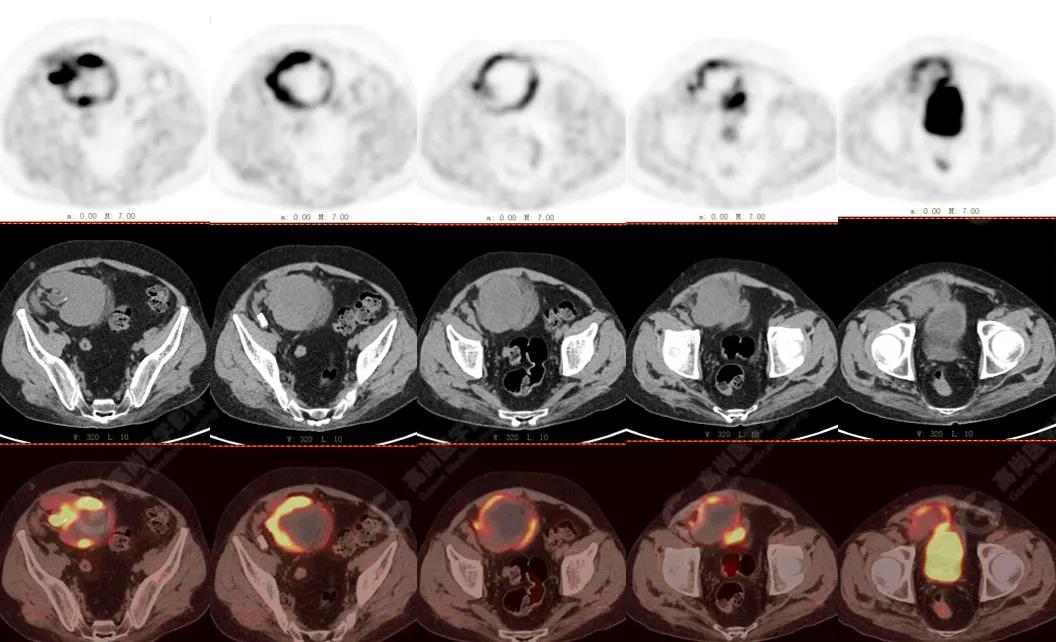

PET/CT檢查

↑移植腎下部等密度腫塊,代謝環(huán)狀增高,SUVmax13.4,中心代謝缺損